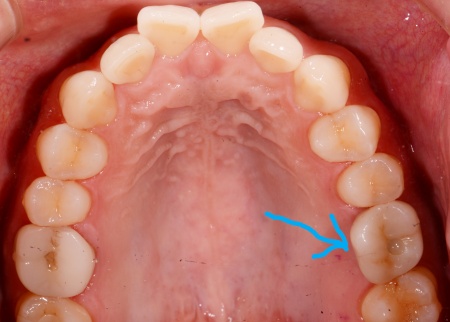

治療後

| 行った治療内容 | 患者様には、歯根が割れた歯の温存が難しく抜歯が必要であることをお伝えしたうえで、以下2つの治療方法を提案しました。 ①顎の骨に人工歯根「インプラント」を埋め込み、その上に被せ物を装着して欠損部を補う メリット:自分の歯のようにしっかりと噛むことができる デメリット:自費診療なので費用が高額になる。手術が必要なため、治療期間が長くなる ②抜歯部位前後の歯を土台として、橋渡しのような被せ物「ブリッジ」を装着する メリット:外科手術を行わないため、治療期間が短くなる デメリット:ブリッジの土台とするために健康な歯を削る必要がある それぞれのメリットとデメリットを丁寧に説明したところ、患者様は①のインプラントを選択されました。 まずはCT撮影を行い、歯や顎の骨の状態を詳しく調べます。 検査の結果、インプラントを埋め込むために必要な骨の量が十分にあることが確認できました。 次に左上奥歯1本を抜き、抜歯と同時にインプラントを埋め込む「抜歯即時埋入法」を用いて、インプラント手術を行います。 この方法であれば外科手術が1回ですむため、治療期間の短縮と噛み合わせの早期回復が可能です。 経過観察後、抜歯時の傷が回復してインプラントと骨がしっかりと結合したことを確認してから、インプラントに装着する被せ物を作製するために精密な型取りを行いました。 被せ物の素材には、耐久性に優れ天然歯のような見た目を再現できるセラミックを選択しています。 後日、完成した被せ物をインプラントに装着し、噛み合わせや使用感に問題がないことを確認して、治療を終了しました。 |